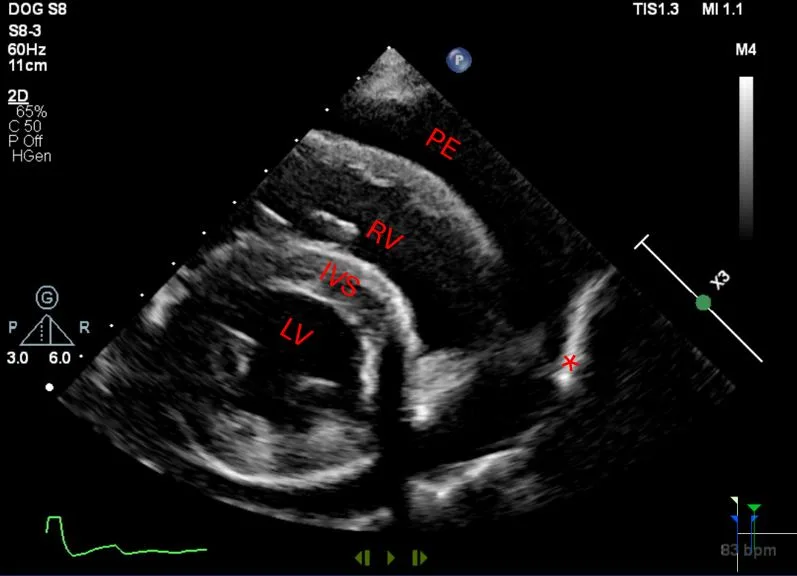

• Echocardiography confirms an echo-free space between the heart and the pericardium (Figure 1), may show cardiac tamponade (Figure 2), and may detect mass lesions.

Four-chamber left apical echocardiographic view showing moderate pericardial effusion with cardiac tamponade. Arrow shows diastolic collapse of the right atrium consistent with cardiac tamponade. (PE = pericardial effusion, LV = left ventricle, RV = right ventricle)

• Evaluate for the presence of cardiac tamponade (eg, diastolic collapse of the right atrium) (Figure 2).